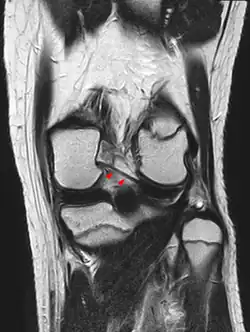

Posterior meniscofemoral ligament on MRI, coronal -

Posterior meniscofemoral ligament (Wrisberg) behind the posterior horn of the lateral meniscus close to its insertion. Sometimes wrongly interpreted as a meniscal tear.